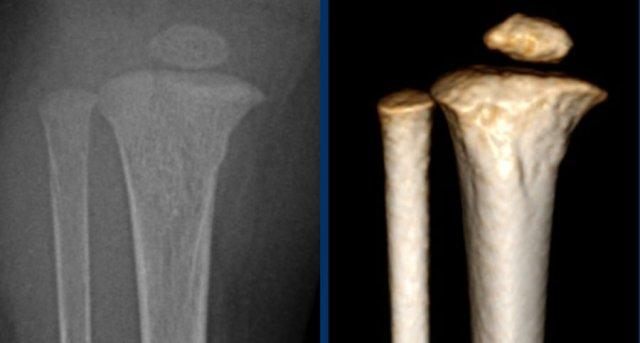

Gãy xương kiểu tay xách xô (Bucket handle fractures)

Gãy xương kiểu tay xách xô về bản chất giống với gãy xương góc.

Mảnh xương bị bong ra có kích thước lớn hơn và được nhìn thấy theo hướng “en face” (nhìn thẳng) như hình đĩa hoặc tay xách xô.

Hình ảnh

Gãy xương kiểu tay xách xô ở đầu trên xương chày. Mảnh gãy hành xương được nhìn thấy như hình đĩa hoặc tay xách xô.